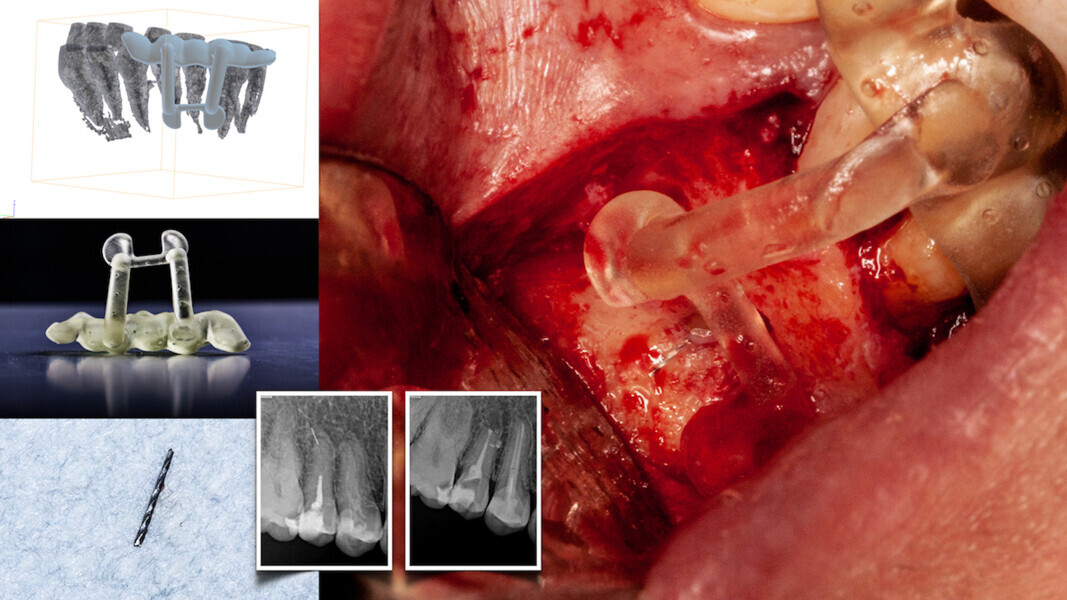

Fig. 4a: The planned axis angulation and orientation of the virtual drill are exacting in targeting calcified canals. (Courtesy of Dr Bobby Nadeau)

Fig. 4b: The red virtual pathway reflects an off-angle positioning. (Courtesy of Dr Bobby Nadeau)

Fig. 4c: Piezotome planning. (Courtesy of Dr Bobby Nadeau)